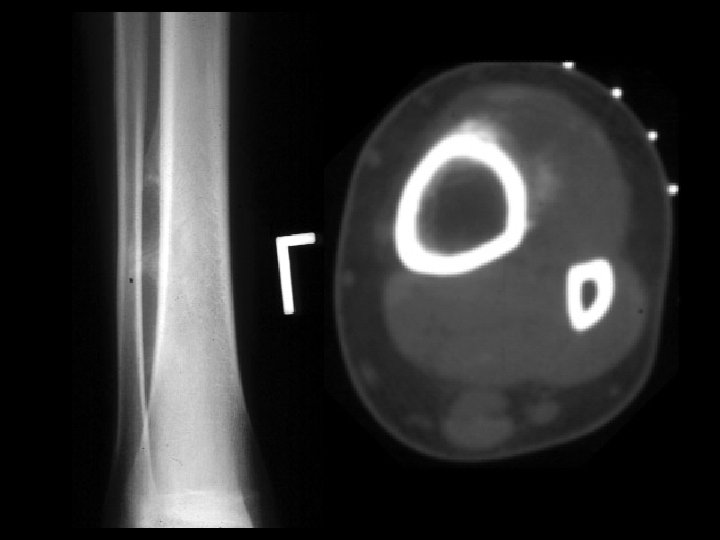

Adamantinoma • Findings: – Expansile mixed lytic and sclerotic lesion of the tibial midshaft – Cortical disruption and periosteal reaction • ddx: – Fibrous dysplasia